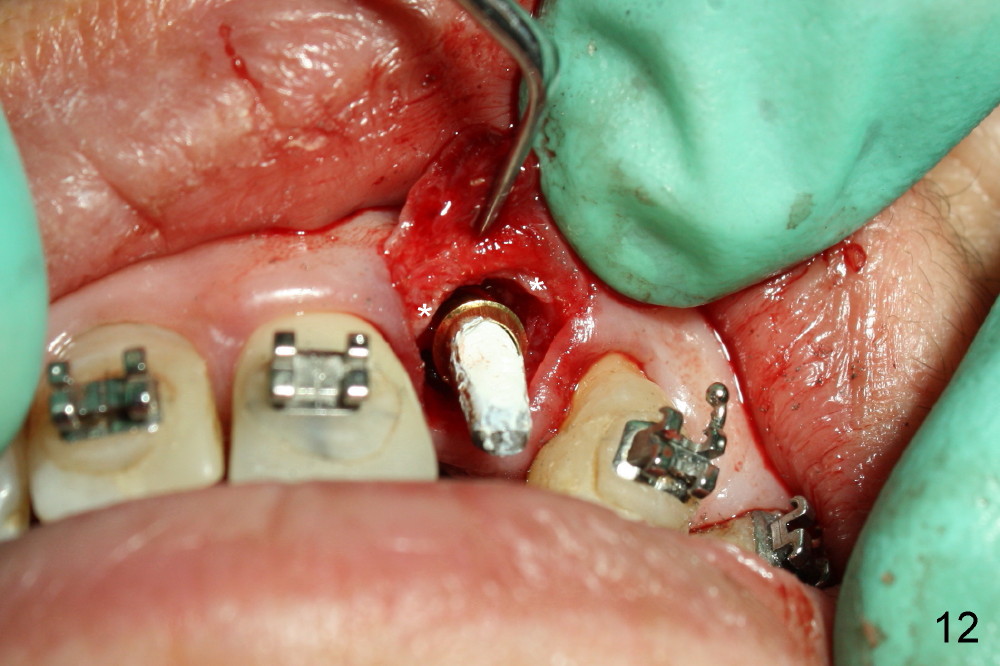

The buccal gap (Fig.11 *) is to be filled by allograft before insertion of an angled abutment (3.9 mm 25 º 3 mm cuff, Torx A type, Fig.12). The shoulder of the abutment is at the crest level (*). A longer cuff (4 or 5 mm) would be more appropriate. The gap buccal to the shoulder of the abutment is closed by further bone graft. An immediate provisional is fabricated (Fig.12 P), followed by suturing the buccal flap (*), which should give bulk of the gingival tissue.